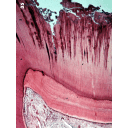

dentinareparativa.png